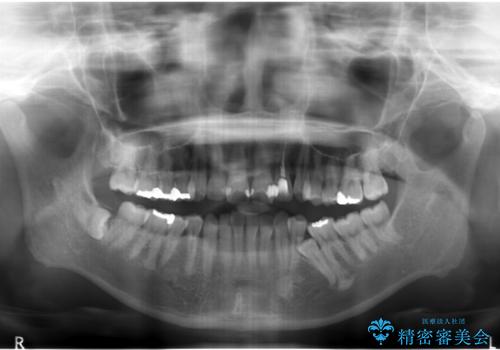

- 前歯のがたつきと左下の歯がうまっているとのことで、矯正治療を希望されました。

埋まっている奥歯を並べることで、その後ろの倒れ込んだ歯を整直させることができました。

引っ張り出すことはマウスピース矯正では難しい為、埋まっている歯を並べるスペース確保と、引っ張り出すのに、ワイヤーを用いた部分矯正を行なっています。

上の歯はマウスピース矯正で、奥歯を後ろに下げて、左のかみ合わせのズレを直しています。

上下とも非抜歯で並べています。

埋まっていた歯をしっかり引っ張り出すことができ、また、前歯の見た目も非常に良くなりました。